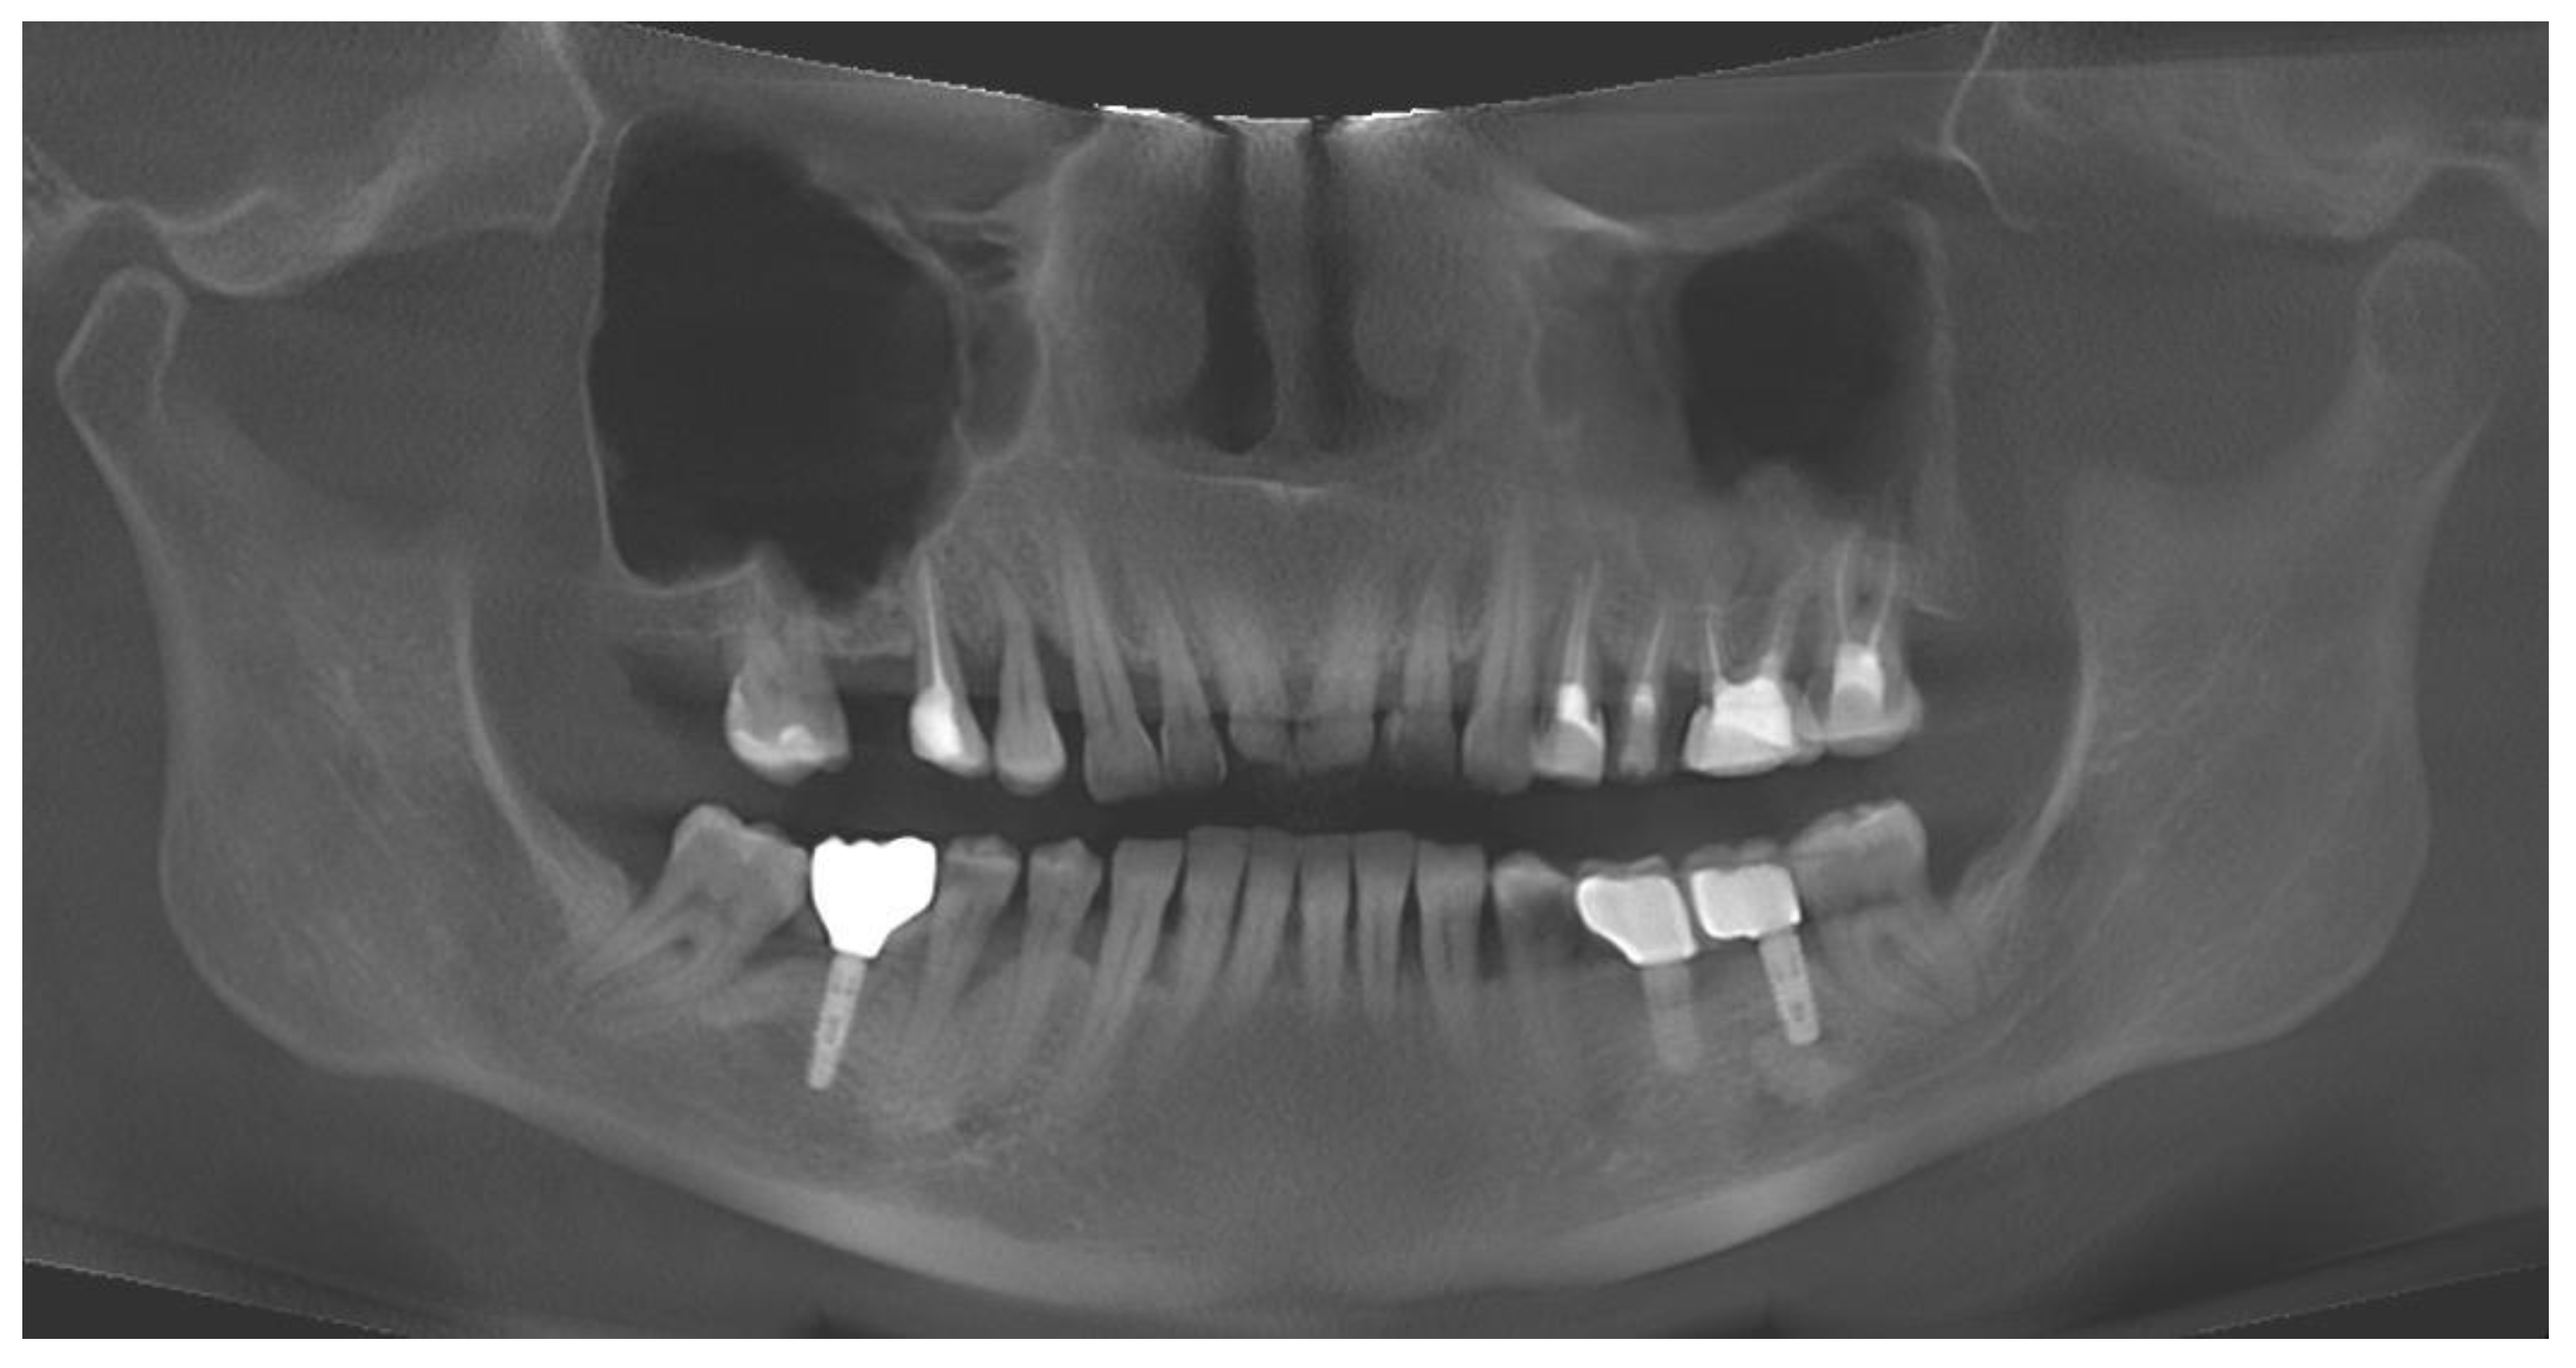

3.1. Case No. 1

3.2. Case No. 2